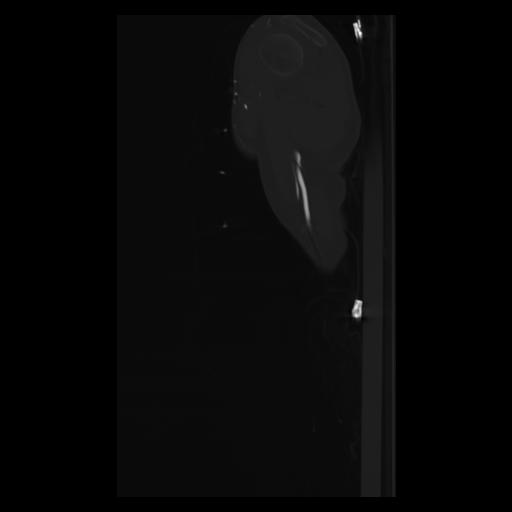

30 CUERPO,CE,Sagittal,3.000,CUERPO,Sagittal,